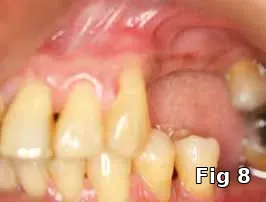

Flap closure management (Figs. 6–11): This patient is a 68-year-old female who has poorly controlled Type 2 Diabetis Melitus (DM) and is a one-pack-a-day smoker and refuses to not wear her partial denture during the primary soft-tissue healing phase (Fig. 6). In cases of possible delayed or compromised healing, using concentrated multifactorial growth factors at the site of injury (Fig. 7) prior to closure (Figs. 8–9) decreases those possibilities and improves and accelerates soft-tissue healing (Figs. 10–11) and diminishes the pain patients feel because of post operative inflammation.